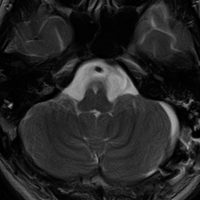

典型的な神経腸嚢胞 neurenteric cyst

左のT2強調画像で等信号,中のT2*で高信号,右はCISS画像です。

T1強調画像では,のう胞周囲の高信号の部分は半固体で,中心部の高信号はドロドロの粘液でした。基本的にガドリニウム増強はされません。まれに薄い膜状に一部が増強されることがあります。

境界明瞭は袋状の腫瘍です。椎骨動脈や脳底動脈を包み込むようにふくらんでいます。